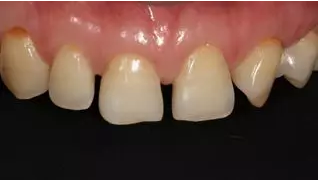

術(shù)后上前牙右側(cè)面照

病例分享|復(fù)合樹脂微創(chuàng)美學(xué)修復(fù)關(guān)閉上前牙間隙